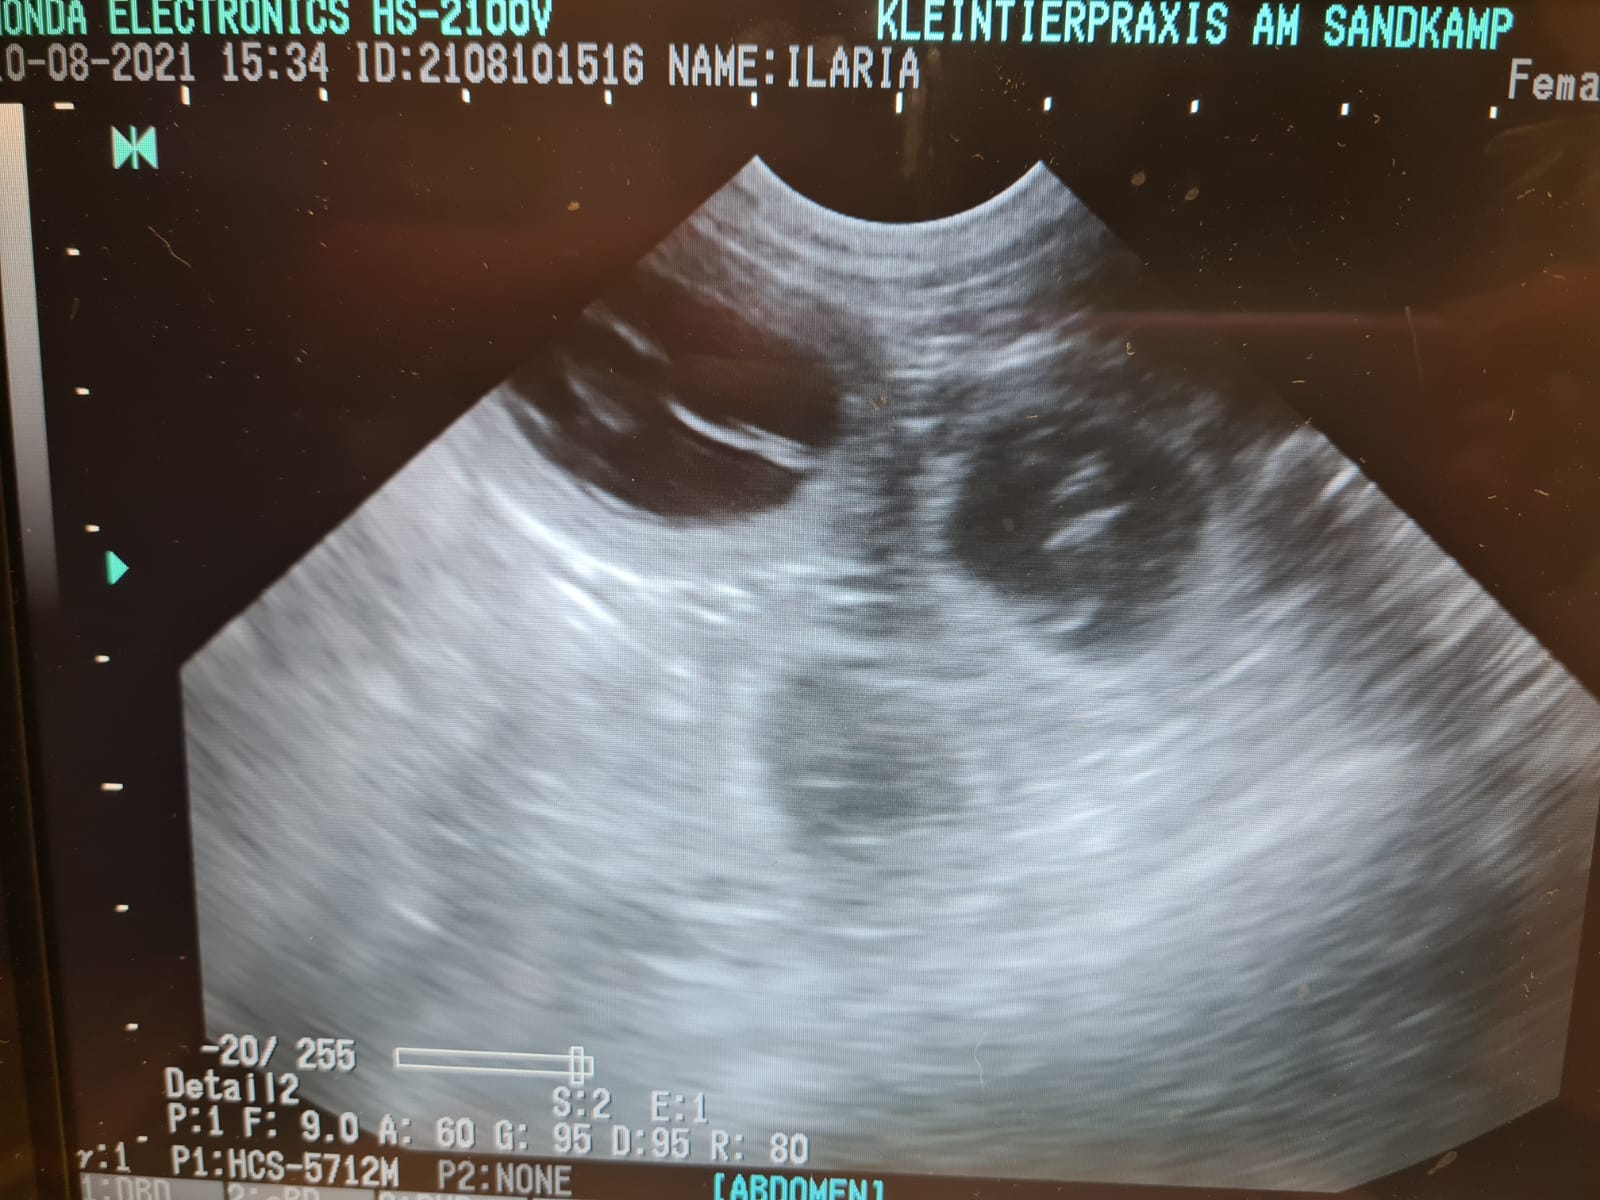

10.08.2021.Wir waren bei der Ultraschalluntersuchung und wissen jetzt sicher das Ilaria aufgenommen hat und unser D-Wurf sich gut entwickelt. Ilaria geht es sehr gut. Wir starten somit in die 5.Trächtigkeitswoche. Wir müssen auf Ilarias Gewicht achten. Die Waage hat mich ertappt. Ich lasse mich von Ilarias Appetit verleiten, naschen zu lassen :-) 15,2kg ist etwas üppig am 33.Tag